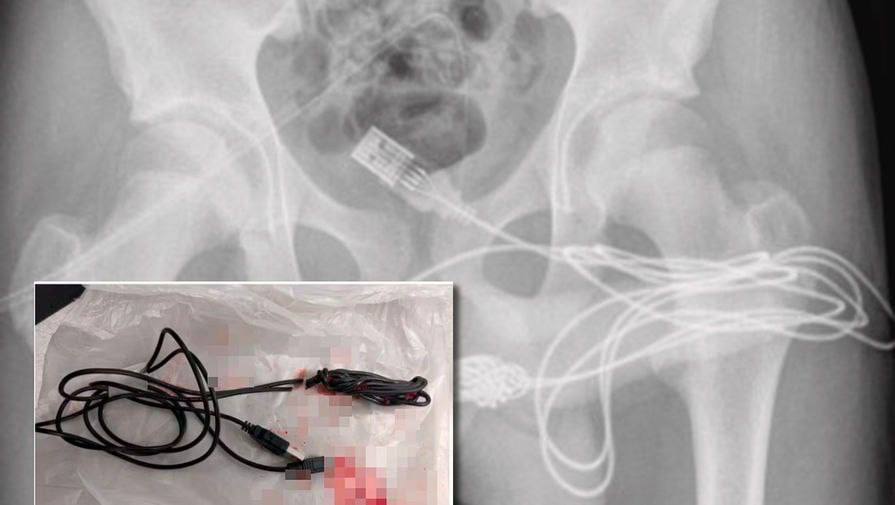

Всовывает в уретру

Всовывает в уретру 111 фотографий